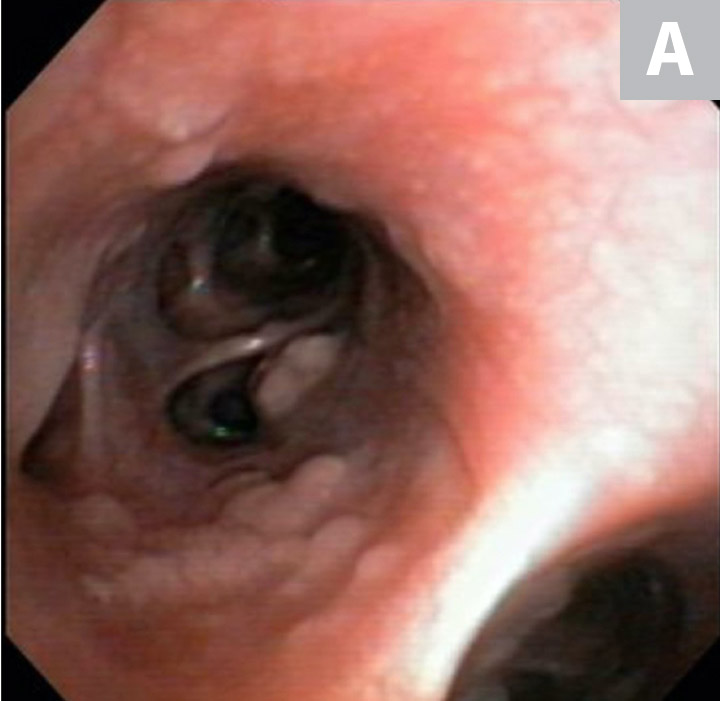

Serum chemistry profile and CBC results were normal, and heartworm antigen test results were negative. Thoracic radiography (right lateral, left lateral, ventrodorsal) revealed a diffuse bronchial pattern but was otherwise unremarkable with no cardiomegaly (vertebral left atrial size, 2.1 [normal, 1.4-2.2]; vertebral heart scale, 9 [normal, 8.7-10.7]) or observable airway collapse (Figure 1). Arterial blood gas showed partial pressure of arterial oxygen 97 mm Hg (normal, 81-103 mm Hg). Echocardiography revealed myxomatous mitral valve degeneration (B1) with no evidence of pulmonary hypertension.2 Laryngoscopy/bronchoscopy showed moderate mucosal irregularity and increased mucus of the lobar bronchi (Figure 2) with normal laryngeal function. Concurrent dynamic bronchial collapse of the left and right mainstem bronchi (grade II/III) was observed (Figure 3).3 Bronchoalveolar lavage was performed and submitted for cytologic evaluation and aerobic culture. Cytology revealed nonseptic neutrophilic inflammation (Figure 4); aerobic culture was negative.